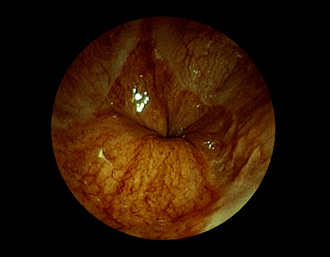

症例9:食道裂孔ヘルニア(84才女性)

胃からの反転観察像で、EGJおよび胃粘膜が食道側への滑脱を認める。